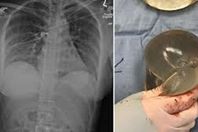

نجاة سيدة من رصاصة قاتلة بسبب حشوة صدر